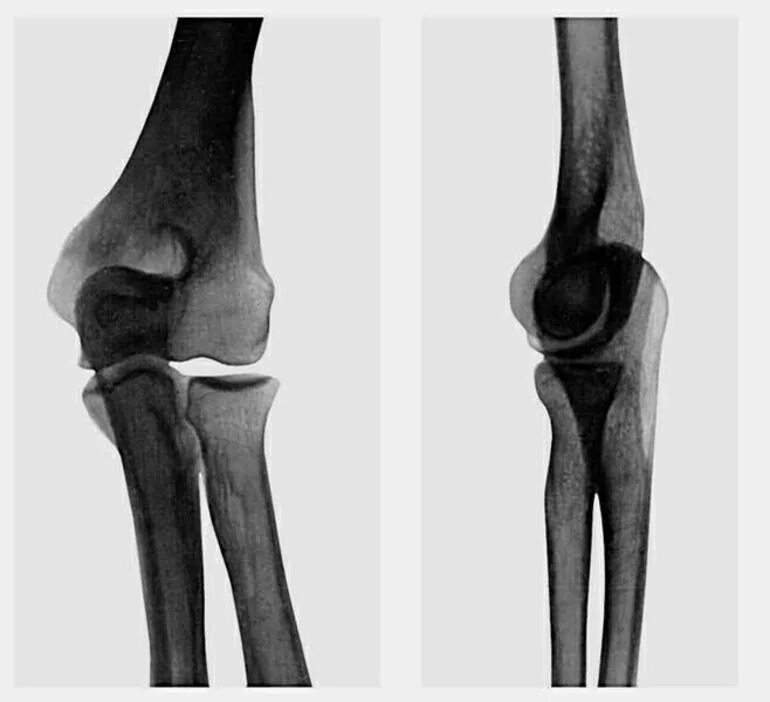

Проекции локтевого сустава